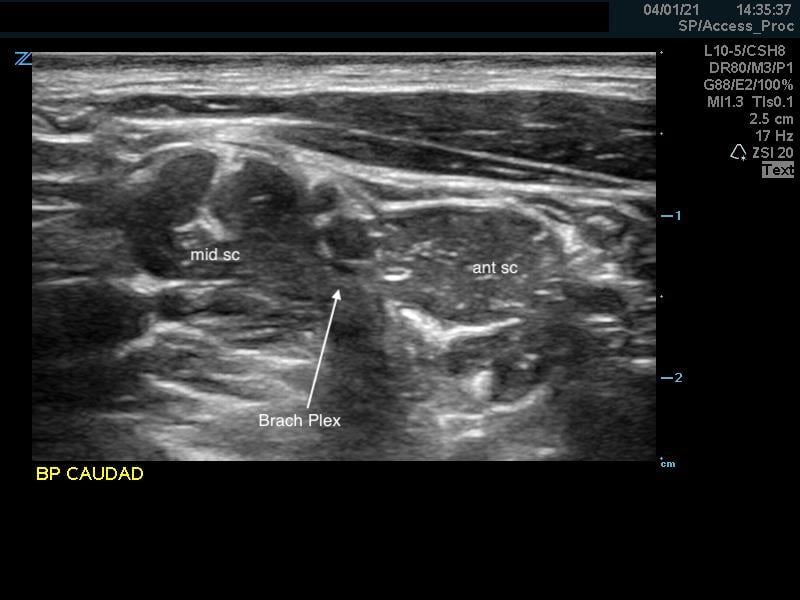

- Alternative Pre-scan – Backtracking from the Supraclavicular Space

- Identify the brachial plexus in the supraclavicular fossa as in the supraclavicular brachial plexus block

- The subclavian artery is the main landmark at this site.

- The brachial plexus is seen immediately adjacent to the superior-posterior border of the subclavian artery as a grouping of small hyperechoic circles with hypoechoic centers, similar to a cluster of grapes.

- Backtrack from this site to the interscalene space by sliding the probe cephalad while keeping the plexus in the center of the image.

- The plexus will change conformation and become more hypoechoic as you slide superiorly.

- May take several passes up the neck and back down to the supraclavicular space.

- Moving the probe quickly may help identify the anatomy.